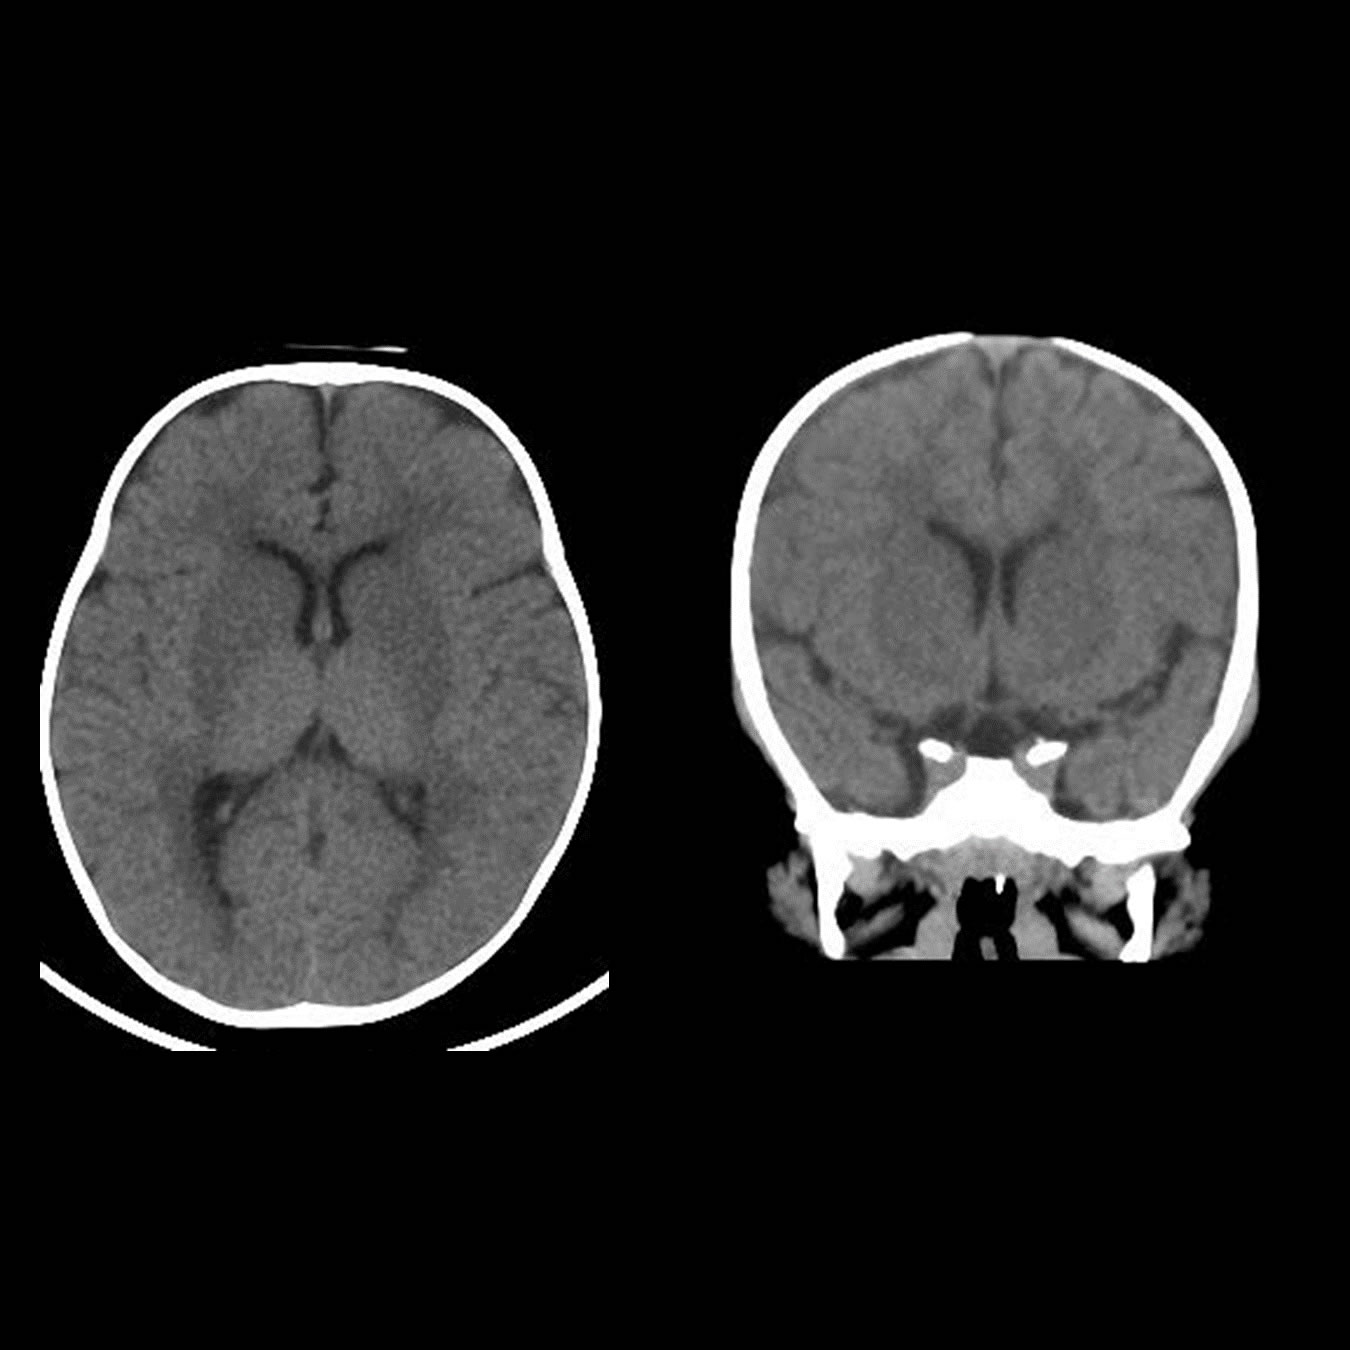

Octubre 2019. Clínica Vélez Sársfield Paciente: femenina de 9 meses de edad Motivo de consulta: episodios convulsivos.